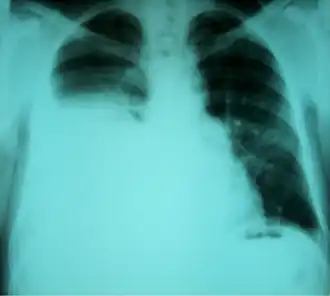

![]() Radiografía de tórax que muestra un hidrotórax hepático en una persona con cirrosis | ||